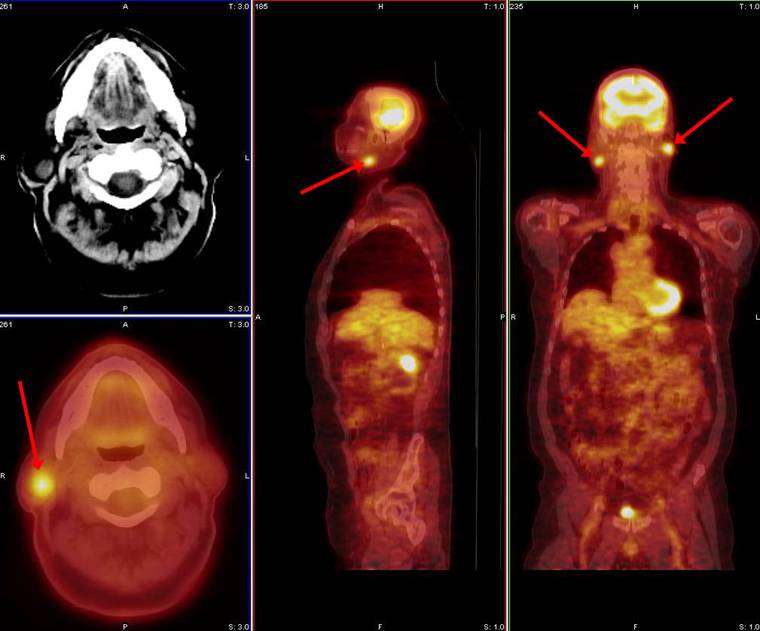

Το PET/CT στο μελάνωμα

To PET/CT είναι σπινθηρογράφημα που χρησιμοποιεί το ραδιοφάρμακο F18-FDG σεσημασμένο με γλυκόζη. Τα καρκινικά κύτταρα έχουν αυξημένο μεταβολισμό και καταναλώνουν πολύ γλυκόζη, η οποία καθηλώνεται στο κύτταρο, λόγω του ότι το μόριο της γλυκόζης που είναι ενωμένο με το ραδιοφάρμακο είναι τροποποιημένο και δεν φωσφορυλιώνεται από το ένζυμο φωσφατάση.

Φυσικά η αυξημένη καθήλωση σημαίνει αυξημένο κυτταρικό μεταβολισμό. Η έντονη καθήλωση εκτιμάται εξατομικευμένα… γιατί η αυξημένη καθήλωση δεν σημαίνει πάντα καρκινική νόσο.

Το PET/CT είναι χρήσιμο σε ασθενείς υψηλού κινδύνου χωρίς ψηλαφητούς ή με ψηλαφητούς λεμφαδένες για έλεγχο υποτροπής και αποκλεισμό απομακρυσμένης νόσου. Συμπληρωματικά θα πρέπει να γίνεται και αξονική τομογραφία για έλεγχο πνευμονικής νόσου (καλύτερα να μη γίνεται)

Άρα σε στάδια ΙΙΙ & V  πρέπει να γίνεται PET/CT SCAN για έλεγχο λεμφαδενικής νόσου ή υποτροπής στα οστά, στο δέρμα, στο ήπαρ και στην κοιλιά, αξονική τομογραφία πνεύμονος για έλεγχο πνευμονικών μεταστάσεων και ολόσωμη MRI για έλεγχο εγκεφαλικών, ηπατικών και μεταστάσεων στο μυελό των οστών.

Όταν η υποτροπή στο μελάνωμα επιβεβαιωθεί το PET/CT SCAN χρησιμοποιείται για ακριβέστερη σταδιοποίηση, ώστε να βρεθεί ποιοι ασθενείς μπορούν να επωφεληθούν από το χειρουργείο.

Άρα το PET/CT SCAN είναι ένα ισχυρό διαγνωστικό εργαλείο και μπορεί να χρησιμοποιηθεί μαζί με άλλες διαγνωστικές μεθόδους και για την παρακολούθηση ασθενών με μελάνωμα εξατομικευμένα (αλλά καλύτερα να μη γίνεται).

Απαιτούνται πολύ πολύ έμπειροι ακτινοδιαγνώστες για να κάνουν διαφοροδιάγνωση μεταξύ φλεγμονής και καρκίνου. Υπάρχουν;